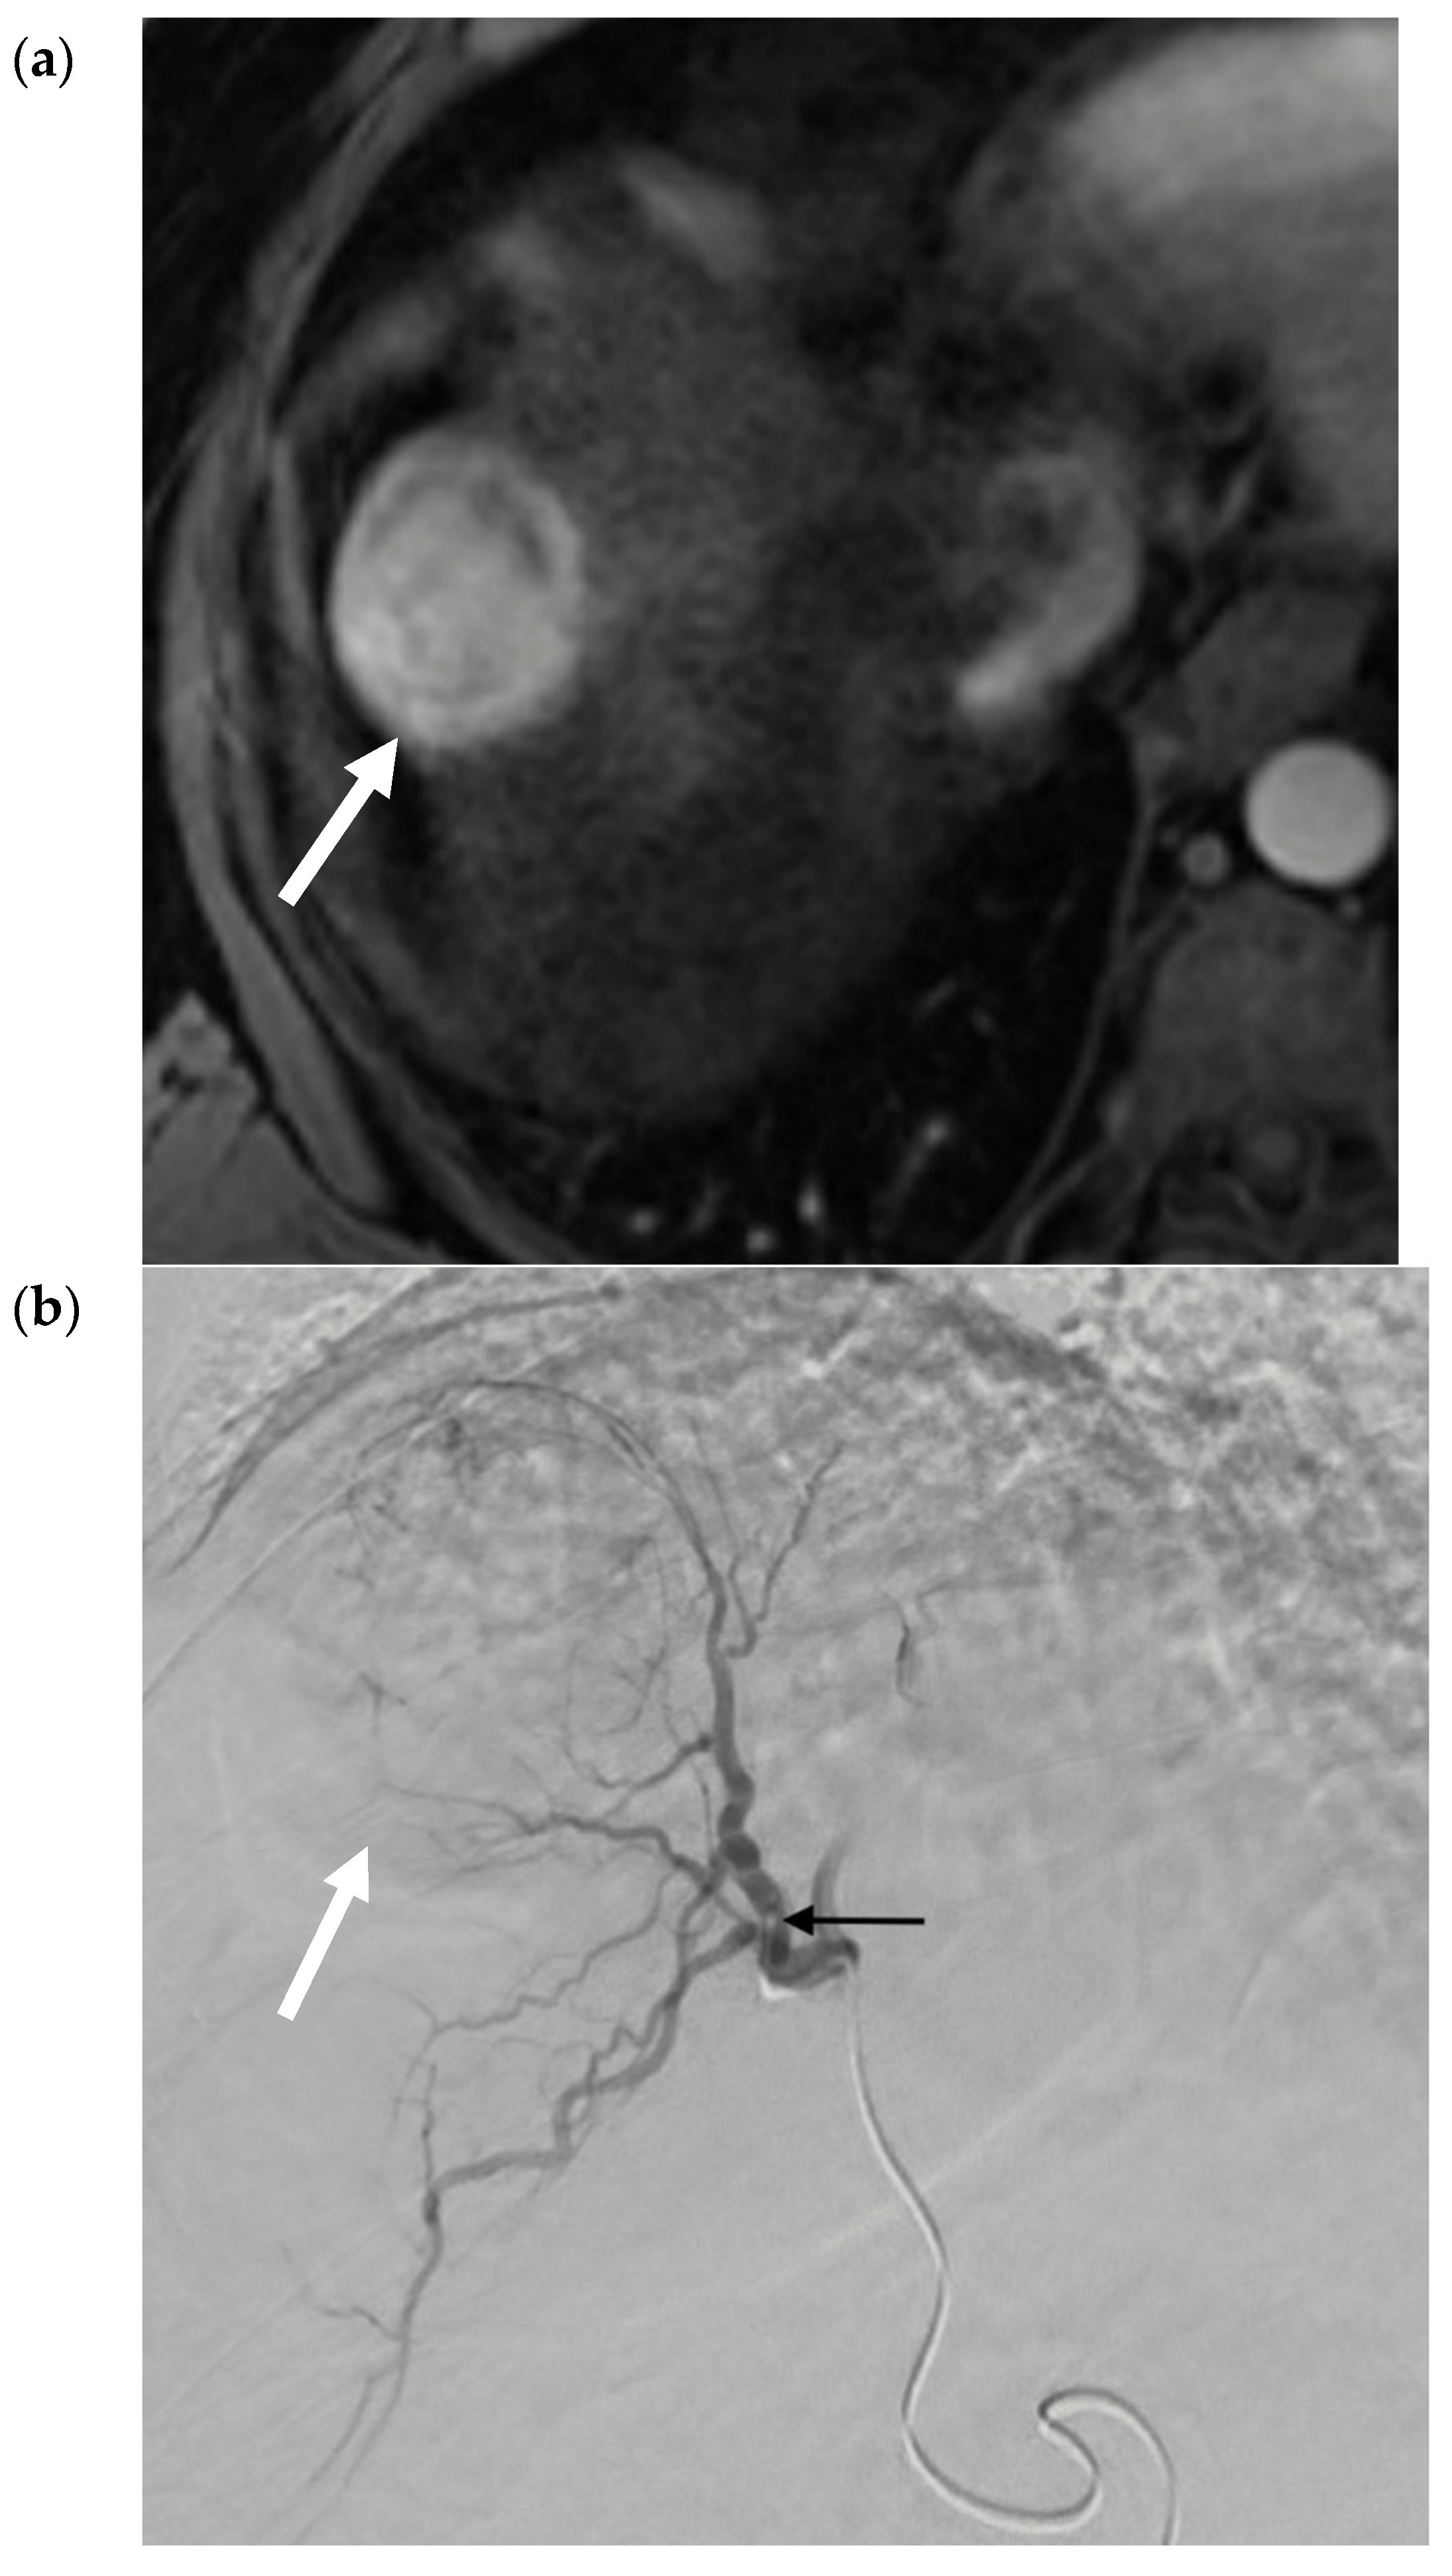

- Vouche, M.; Habib, A.; Ward, T.J.; Kim, E.; Kulik, L.; Ganger, D.; Mulcahy, M.; Baker, T.; Abecassis, M.; Sato, K.T.; et al. Unresectable solitary hepatocellular carcinoma not amenable to radiofrequency ablation: Multicenter radiology-pathology correlation and survival of radiation segmentectomy. Hepatology 2014, 60, 192–201. [Google Scholar] [CrossRef]

- Biederman, D.M.; Titano, J.J.; Korff, R.; Fischman, A.; Patel, R.S.; Nowakowski, F.S.; Lookstein, R.; Kim, E. Radiation Segmentectomy versus Selective Chemoembolization in the Treatment of Early-Stage Hepatocellular Carcinoma. J. Vasc. Interv. Radiol. 2018, 29, 30–37. [Google Scholar] [CrossRef]

- Lewandowski, R.; Gabr, A.; Abouchaleh, N.; Ali, R.; Al Asadi, A.; Mora, R.; Kulik, L.; Ganger, D.; Desai, K.; Thornburg, B.; et al. Radiation Segmentectomy: Potential Curative Therapy for Early Hepatocellular Carcinoma. Radiology 2018, 287, 1050–1058. [Google Scholar] [CrossRef]